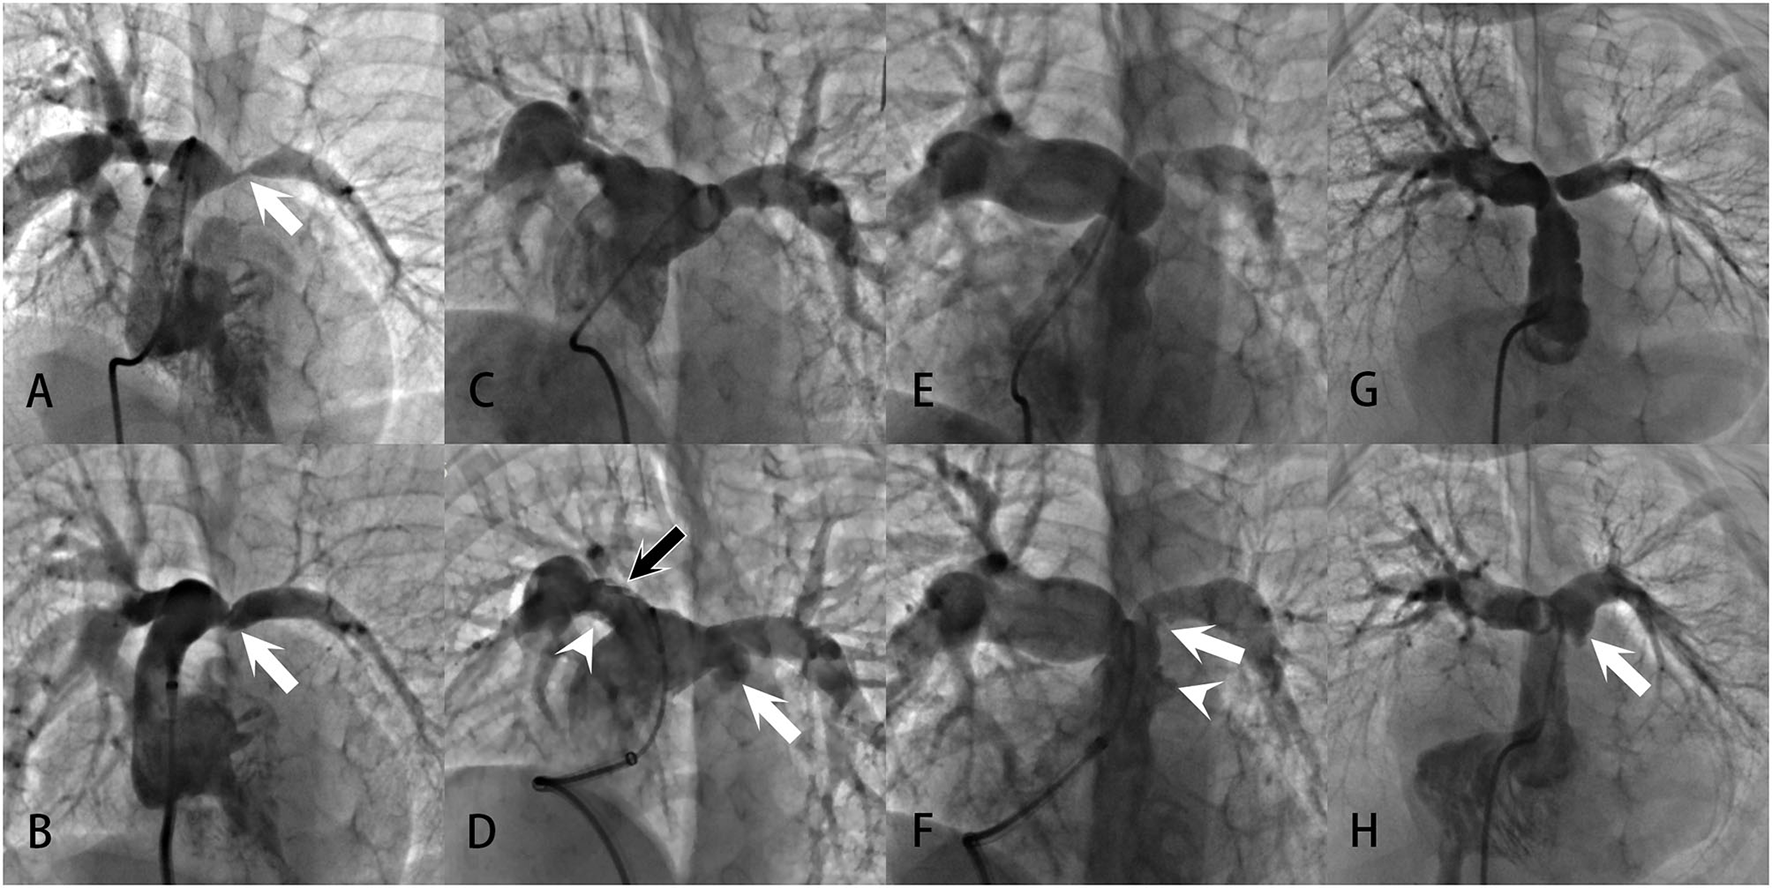

No perioperative death occurred. During the procedures, no hemodynamic instability was recorded in any patient. Perioperative acute adverse events were recorded in 16 patients, with 11 cases of pulmonary artery injuries, three cases of pulmonary hemorrhage, and two cases of pulmonary artery aneurysm. Pulmonary artery injuries occurred after nearly 30% of the total angioplasties. Most of them, nevertheless, were signs of therapeutic tears, such as pulmonary artery vessel tears, vessel extravasations, and vessel intimal flaps (Figure 2). At the dilation site, various degrees of localized dilation were present. It was not considered an aneurysmal formation until the luminal diameter exceeded two times the adjacent normal vessel (Figure 2) and the two aneurysms showed no signs of rupture. All three pulmonary hemorrhage cases were treated with conservative strategies, including mechanical ventilation with positive end-expiratory pressure and hemorrhages resolved within 53 h. Neither pulmonary edema nor any new arrhythmias were noticed in this series. No emerging or aggravated tricuspid and pulmonary regurgitations were seen after the procedures.

Figure 2

Examples of pulmonary artery injuries and formation of pulmonary artery aneurysms demonstrated in the angiograms: (A, B) Severe left PAS in a patient with repaired UAPA. After successful angioplasty, the vessel showed intimal irregularities (white arrow), a sign of vessel tear at the intima and media. (C, D) Bilateral branch PASs in a patient with repaired PA/VSD. After angioplasty, intimal irregularities (white arrowhead) and multiple filling defects (black arrow) were present at the upper and lower edge of the right pulmonary artery. Swinging of the filling defects with the cardiac cycle could be seen in the vessel, suggesting the formation of intimal flaps. Vessel extravasation occurred at the left pulmonary artery (white arrow). These were all signs of vessel tears. And the extravasation was large enough to meet the criteria of a pulmonary artery aneurysm. (E, F) Prominent PASs at the main and left pulmonary arteries in a patient with repaired ToF. After angioplasty, there were vessel intimal irregularities and extravasation at the main pulmonary artery (white arrowhead), indicative of vessel tear. An intimal flap was noted at the left pulmonary artery (white arrow). (G, H) Left PAS in a patient with repaired PA/VSD. After angioplasty, localized vessel extravasation and aneurysm formation was noted at the left pulmonary artery (white arrow).